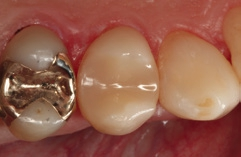

Die Weiterversorgung erfolgte nach adhäsiver Vorbehandlung mit einem approximal eingebrachten 4-mm-Inkrement SDR flow+ (Dentsply Sirona) in der Farbe A3, klassisch überschichtet mit ceram.x universal in der Farbe A3,5. Die Wahl auf ein Bulk-Flow-Komposit approximal fiel aufgrund der optimalen selbstnivellierenden Adhäsion zum Adhäsiv und somit zur Reduktion potenzieller Fehlerquellen in der Schichttechnik, die Wahl zugunsten des eingefärbten SDR flow+ in der Farbe A3 entgegen der transluzenten Universalfarbe U aufgrund der im Approximalraum dunkel erscheinenden Gold-Restauration am Nachbarzahn. Dies ergab in der Vergangenheit bei Verwendung von SDR flow+ U oft ein unschönes „grau-transluzent“ erscheinendes Bild der Kompositrestauration im Approximalraum. Ästhetisch störte dies meist nur bedingt, suggerierte aber immer die latente Möglichkeit einer Approximalkaries. Durch die Verwendung der Farbe A3 bei SDR flow+ war ein derartiges grau-transluzentes Erscheinungsbild nicht mehr gegeben; die Restauration erscheint homogener (Abb. 5). Die Abbildung 6 zeigt die Röntgenkontrollaufnahme nach einem Jahr, die Abbildung 7 die klinische Situation: Der Zahn ist weiterhin vital, symptomlos und beschwerdefrei. Direkte Kompositrestaurationen stellen heute gerade bei vorangegangenen Goldinlay-Kavitäten die suffizienteste Sekundärversorgung dar: Der vorhandene Federrand kann belassen werden und muss nicht in eine plane Stufe einer Keramikrestauration umpräpariert werden.

Im Röntgenbild ist kein Unterschied in der Röntgenopazität zwischen SDR flow+ und ceram.x universal auszumachen, obwohl 2/3 der approximalen Kavitätentiefe von SDR flow+ ausgefüllt wird. Da hinsichtlich ihres Indikationsspektrums direkte Kompositrestaurationen eine ideale Alternative zu Inlayversorgungen darstellen und zudem substanzschonender sowie kosteneffizienter sind, bleibt heute kaum mehr eine wahre Indikation für Inlayversorgungen. Klinisch bewährt hat sich die direkte Kompositversorgung gerade bei dem Austausch kleinerer Goldinlays [13,14].